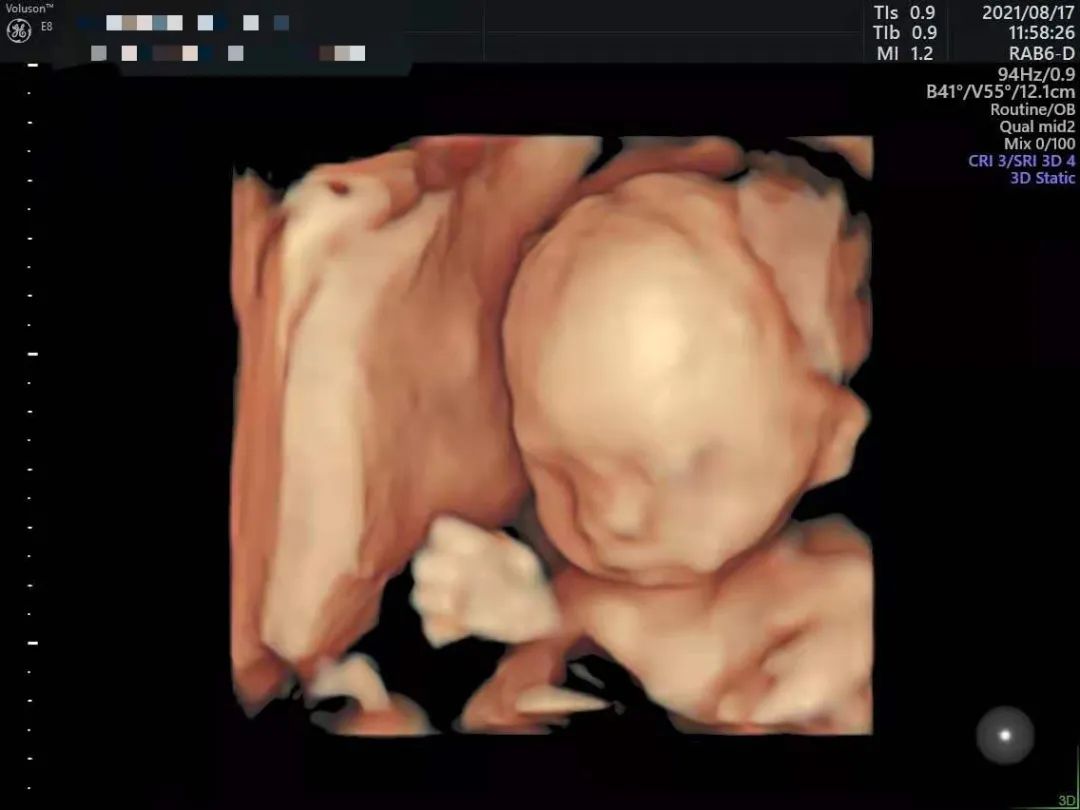

做四维只关心照片清不清晰?比清晰度更重要的其实是……

通过四维可以“看”到什么

做过四维的妈咪都知道,要是刚好碰到宝宝趴着身子或是捂着小脸,妈妈们可就免不了狂吃甜食或来回运动、爬楼梯的一番折磨 。不过在和平的二楼导乐体验区域,助产士会根据准妈妈自身情况,运用专业医疗手法个性化调整胎位,帮助妈妈们一次看清宝宝正脸!

。不过在和平的二楼导乐体验区域,助产士会根据准妈妈自身情况,运用专业医疗手法个性化调整胎位,帮助妈妈们一次看清宝宝正脸!